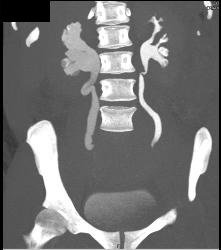

Dilated Right Ureter and Renal Pelvis With CT Urography